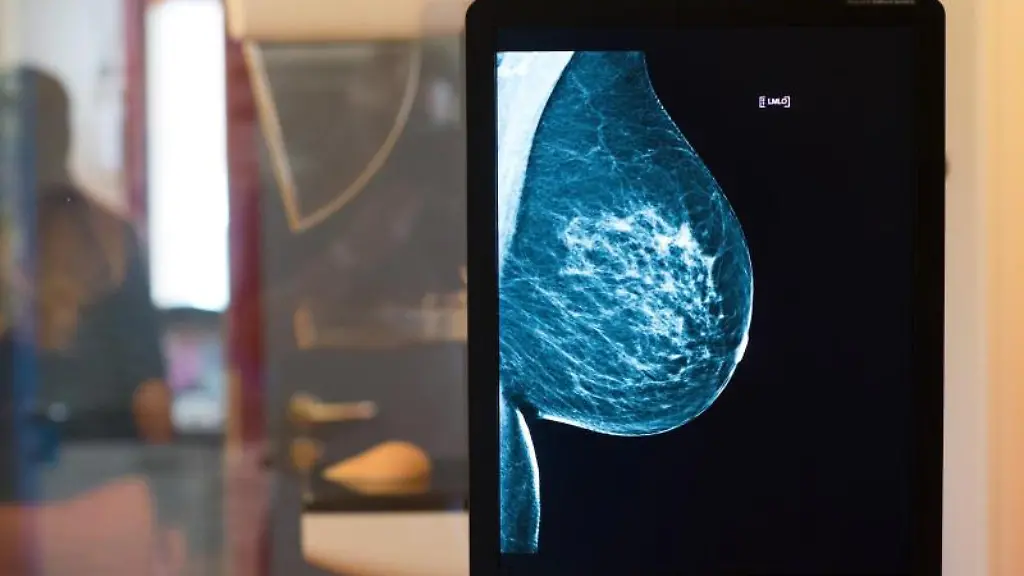

In Deutschland werden Frauen im Alter zwischen 50 und 69 Jahren alle zwei Jahre schriftlich zur Mammografie eingeladen. Bei der Untersuchung werden zwei Röntgenaufnahmen von der Brust gemacht. Dabei wird die Brust zwischenzeitig zusammengedrückt, was schmerzhaft sein kann - aber harmlos ist. So können schon sehr kleine, nicht tastbare Tumoren früh erkannt werden. Fachleute sprechen bei solchen Routineuntersuchungen Gesunder auch von "Screening".